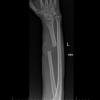

Plain film radiographs (Fig. 1) demonstrated an oblique fracture of the proximal third of ulna shaft with an apex anterior angulation of 30° and a Salter-Harris Type I fracture through the proximal radial physis with an anteriorly displaced proximal metaphysis. The proximal radial epiphysis however appeared to be congruent with the capitellum in orthogonal views.